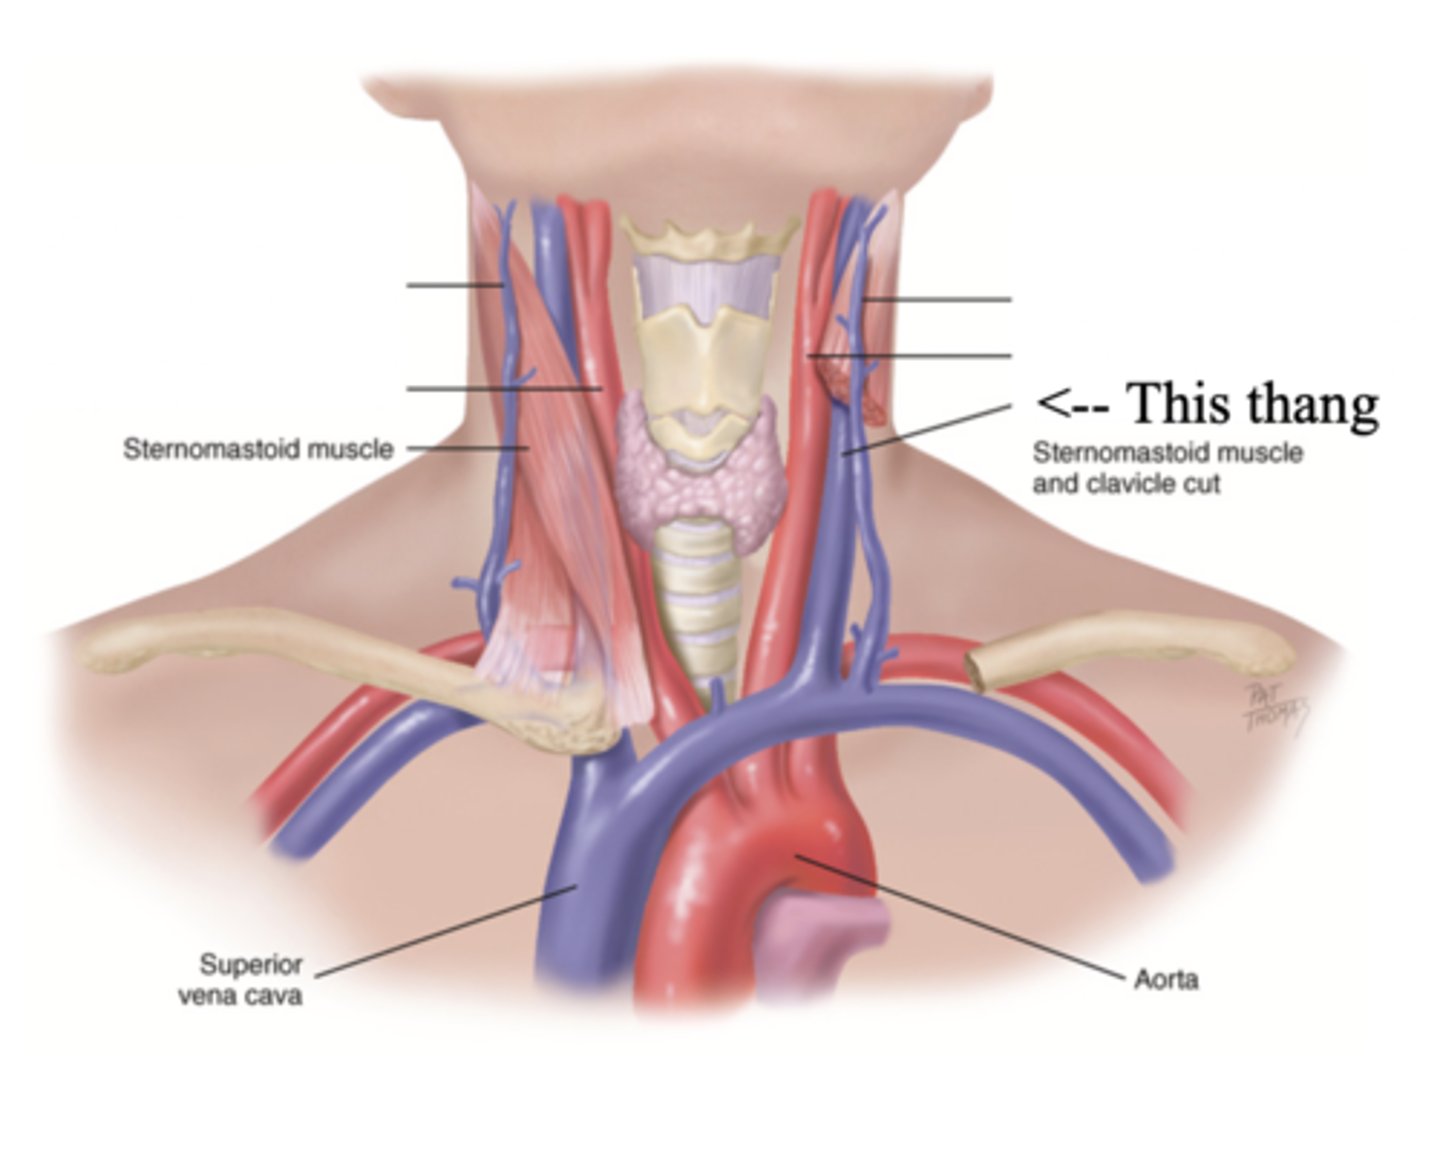

2 Main Neck Vessels

- Jugular veins

- Carotid arteries

Jugular Veins

- One of the main neck vessels; carries unoxygenated blood to the superior vena cava

- Has 2 parts

- Provides information about activity of right side of heart

2 Parts of the Jugular Veins

- External

- Internal

External Jugular Veins

The more superficial jugular vein that lies lateral to the sternocleidomastoid and above the clavicle

Internal Jugular Veins

The deeper jugular vein that lies medial to the sternocleidomastoid

Carotid Arteries

The major neck vessel that carries oxygenated blood from the heart to the head

Main Differences Between Internal Jugular Veins and Carotid Arteries

- Internal jugular pulse more lower and lateral to sternocleidomastoid than the carotid pulse, which is higher and more medial

- Internal jugular pulse is more undulant and diffuse, while carotid pulse is more brisk and localized

- Internal jugular pulse varies with respiration

- Carotid pulse can be palpated

- Palpating internal jugular pulse will obliterate it

- Internal jugular pulse drops/disappears as the patient is brough to a sitting position